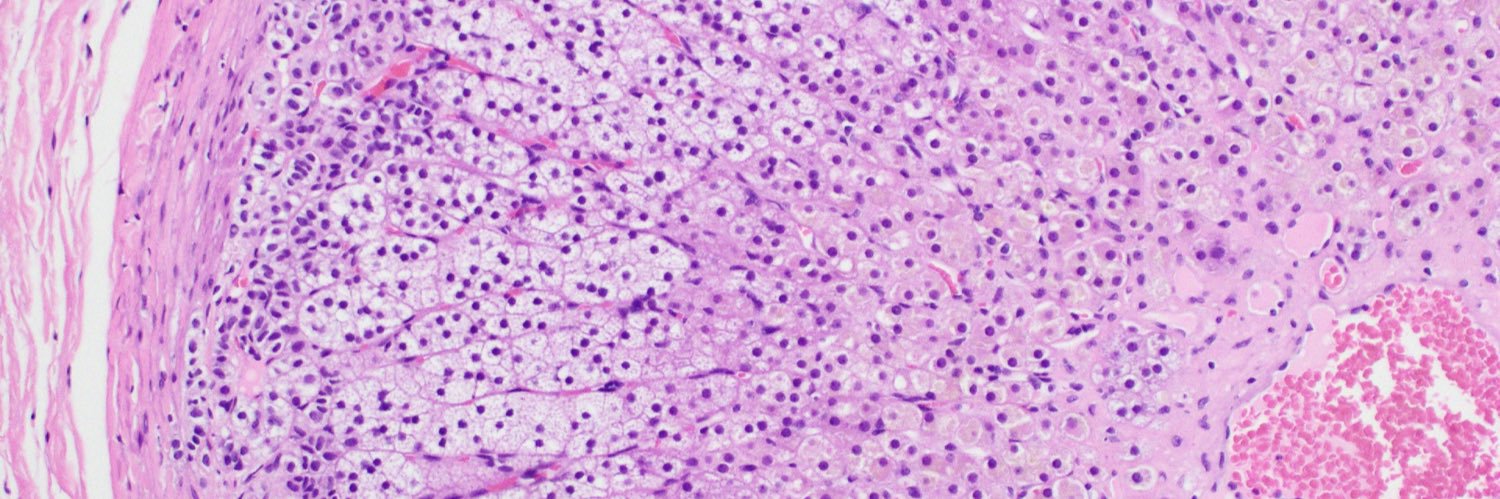

🔬Happy Monday, Twitterverse! We at the Path dept of AMC want to help educate residents and fellow learners alike to showcase the interesting world of pathology. We will strive to present an unknown case once at least every two weeks. Can you guess the diagnoses?🤔 #pathtwitter